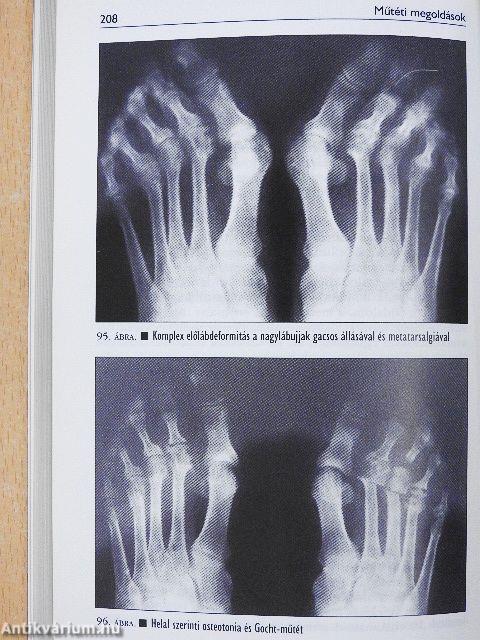

A komplex előlábdeformitások műtétei206

Metatarsalgia207

Rezekciós arthroplasticák a metatarsophalangeális ízületekben213